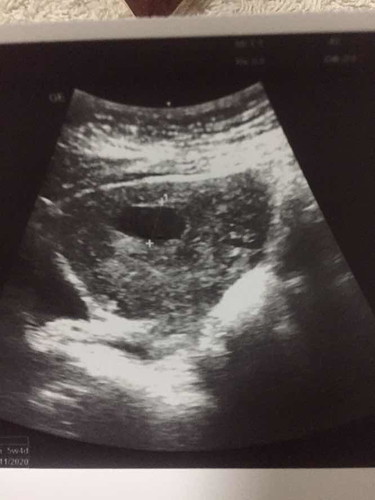

ยังไม่เห็นตัวอ่อน

6week เเล้ว คุณหมอบอกยังไม่เห็นตัวอ่อนเลย คะ ?

ซาวผ่านหน้าท้องหรือช่องคลอดคะ บ้านนี้ตอน6week ซาวผ่านหน้าท้องไม่เจอตัว เจอแต่ถุง คุณหมอเลยซาวผ่านช่องคลอดด้วย จะเอ๋เจอตัวเป็นๆเลยค่ะ เล่นซ่อนแอบเก่งแต่ในท้อง